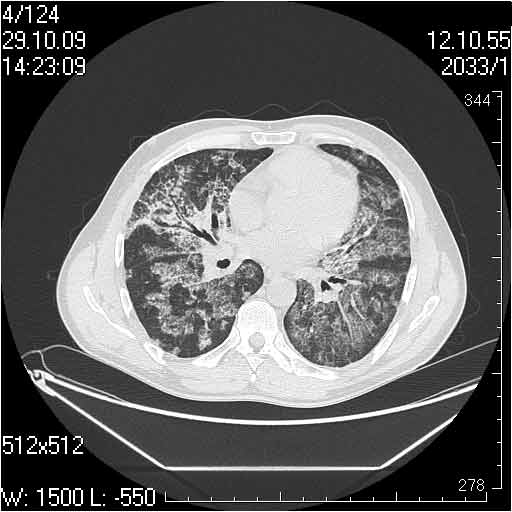

Случай №2

Мужчина 54 лет

Случай 2: картина патологических изменения довольно типична: GGOs & thickened interlobular septas = "crazy paving" sign. Наличие плотностей по типу матового стекла в сочетании с утолщением междолевых перегородок, даёт признак булыжной мостовой; на первом месте будет стоят диагноз альвеолярных протеиноз.